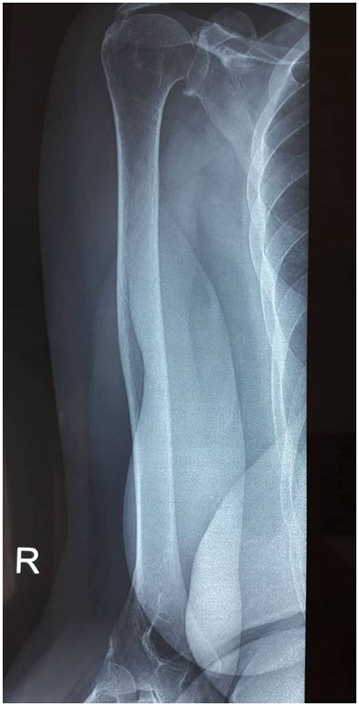

The presence of hypogammaglobulinemia gave rise to the initial diagnosis of humoral hypercalcemia of multiple myeloma. Subsequently, a radiological evaluation of the skeleton was undertaken and showed a well-defined lytic lesion at the middle of the humerus. The absence of anaemia or renal insufficiency and the absence of electrophoretic signs of monoclonal secretion in the blood or urine eliminate this diagnosis. The others biochemical indices confirmed the diagnosis of PHPT: hypercalcemia at 11.9mg/dL (8.4–10.2mg/dL), serum hypophosphatemia at 1.54mg/dL (2.7–4.5mg/dL), and elevated parathyroid hormone rate at 584pg/mL (10–88pg/mL). We noted a serum 25OHD deficiency at 8.4μg/L (30-70g/L). At subsequent radiological work-up, both ultrasonography and computed tomography of her neck revealed a right parathyroid adenoma. We concluded posterior that the humeral lesion was in fact a Brown tumor (Figure 1).

They can occur in any location but are most common in the ribs, clavicle and pelvis.6,7 Our case is characterized by an atypical and unique localization in humerus. As in our observation, on radiological examination they appear as osteolytic lesions with well-defined borders.8 It is noteworthy that its radiological and histopathological features may be mistaken for other bony pathologies.3,9–12